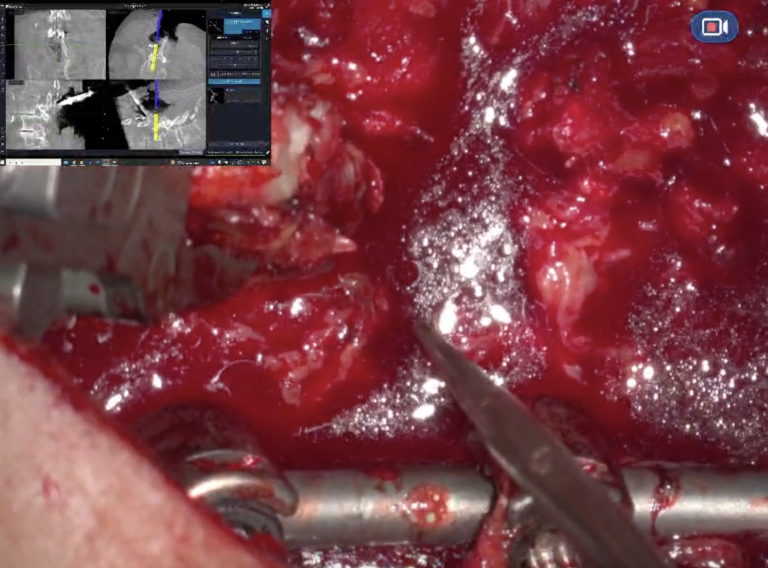

By integrating the RoboticScope with the neuronavigation system Stealthstation S8 from Medtronic, surgeons gain a comprehensive view through the Head-Mounted Display, allowing seamless transitions between macroscopic and microscopic views.

With the RoboticScope's VideoIn function, images from the RoboticScope and the neuronavigation system are transmitted simultaneously to the Head-Mounted Display (HMD).

3. Microscopic Decompression: The RoboticScope is positioned over the surgical field, allowing for microscopic decompression of the spinal canal. Surgeons control the RoboticScope’s camera through intuitive head movements, which adjusts zoom, focus, and field of view without interrupting the flow of surgery.